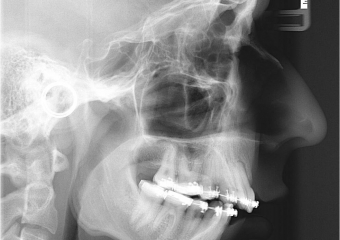

Telerradiografia inicial